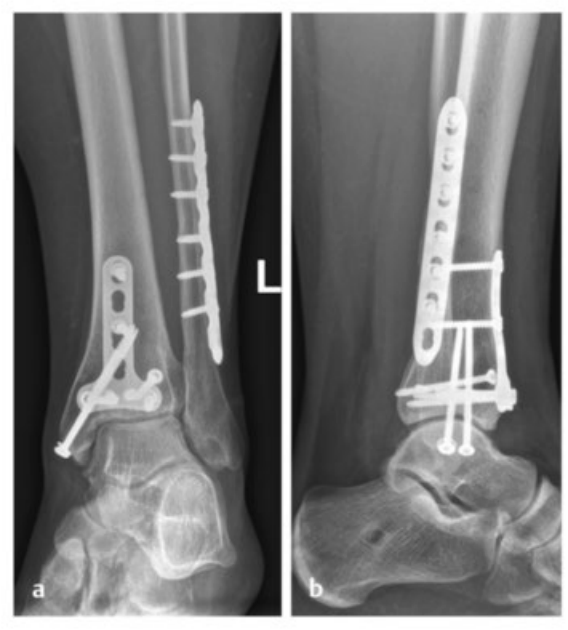

病例2受伤后入院首先植入跨踝关节外固定架,待软组织肿胀消退后,先对腓骨骨折进行微创固定,随后逐步完成复杂的胫骨Pilon骨折复位与固定。

术中临床图像显示了损伤的严重程度,同时体现了微创手术技术的优势,以及在必要时下胫腓联合切开复位重建的重要性。借助斯氏针的 “操纵杆(Joy-Stick)” 技术,可显著简化关节面的复位操作。

术后影像学随访检查显示骨折解剖复位,内植物位置良好。

患者术后恢复顺利,关节功能良好。术后12个月取出内植物,未发现创伤后关节炎征象。